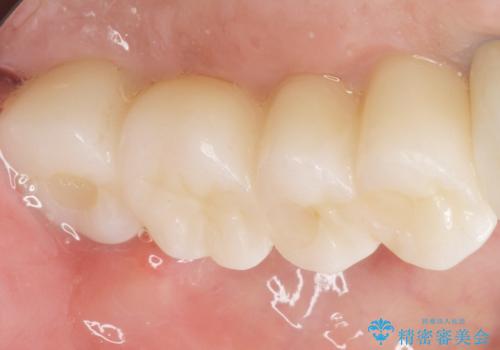

奥歯でしっかりと咬むことができるようになり、喜んで頂けました。

角化歯肉の移植により、ブラッシング時の歯ぐきの痛みもなくセルフコントロールも良好です。

クラウンの種類:ベレッツァクラウン